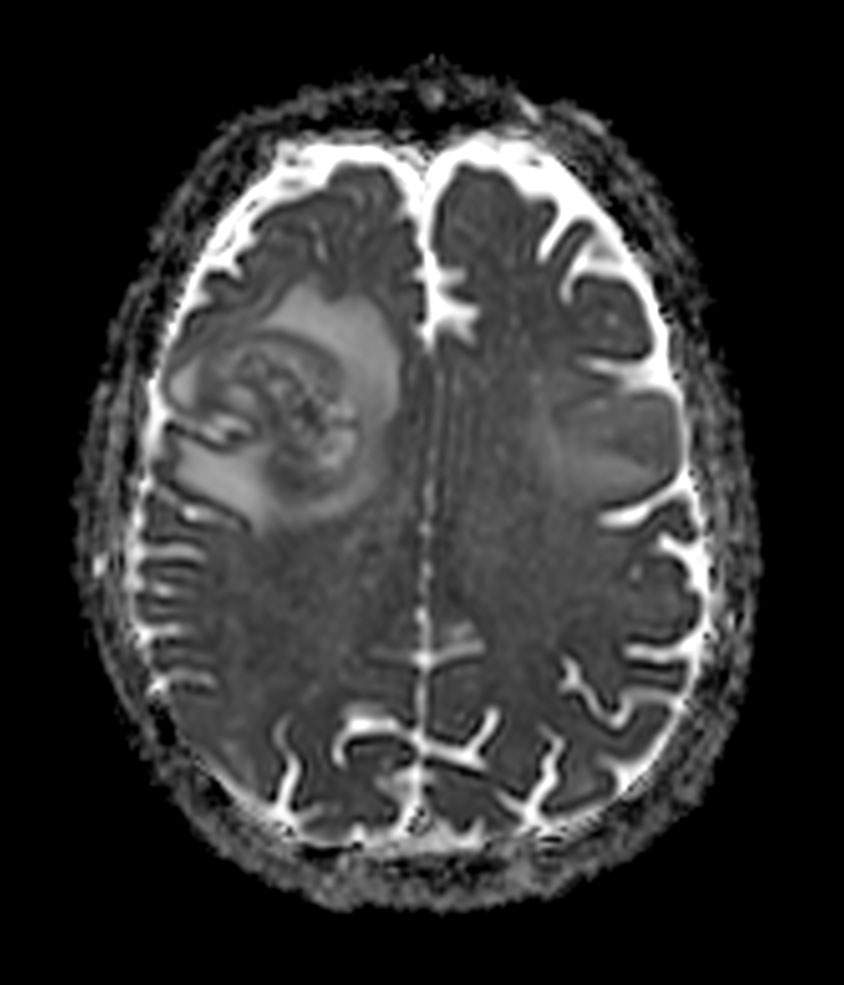

Axial T2w MultiVane XD

Axial 3D BrainVIEW FLAIR